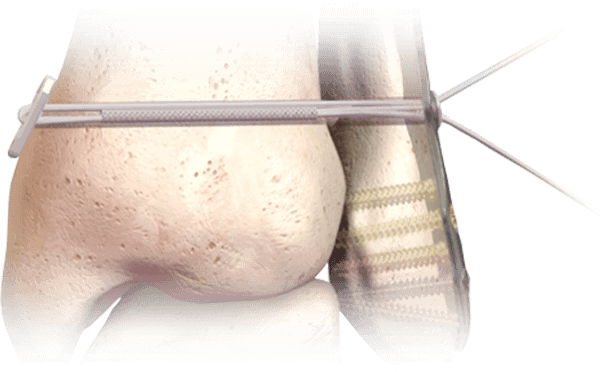

Hercules® Sistema de Implantes de Sindesmosis Sin Nudos

Una alternativa de perfil bajo y sin nudos a la fijación con tornillos rígidos para lesiones sindesmóticas y estabilización del mediopié.

Aplicaciones:

- Alteraciones de la sindesmosis (fracturas de tobillo Weber B/C)

- Complemento para la corrección del hallux valgus

- Estabilización de la articulación del mediopié y del antepié

Ventajas Clave:

- Sutura de UHMWPE tensada entre botones de aleación de titanio de perfil bajo

- Permite el micromovimiento para apoyar la biomecánica de curación natural

- Entregado en un kit estéril de un solo uso

- Compatible con placa o uso independiente